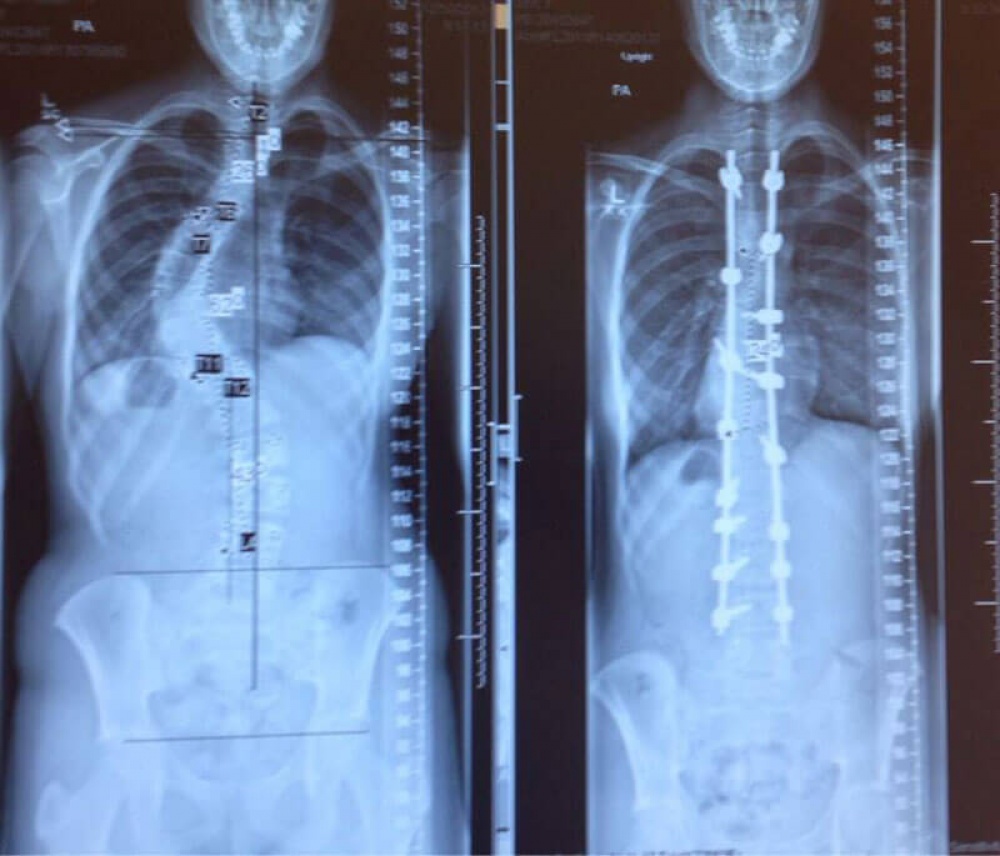

4. O radiografie a coloanei cuiva înainte și după tratamentul pentru scolioză